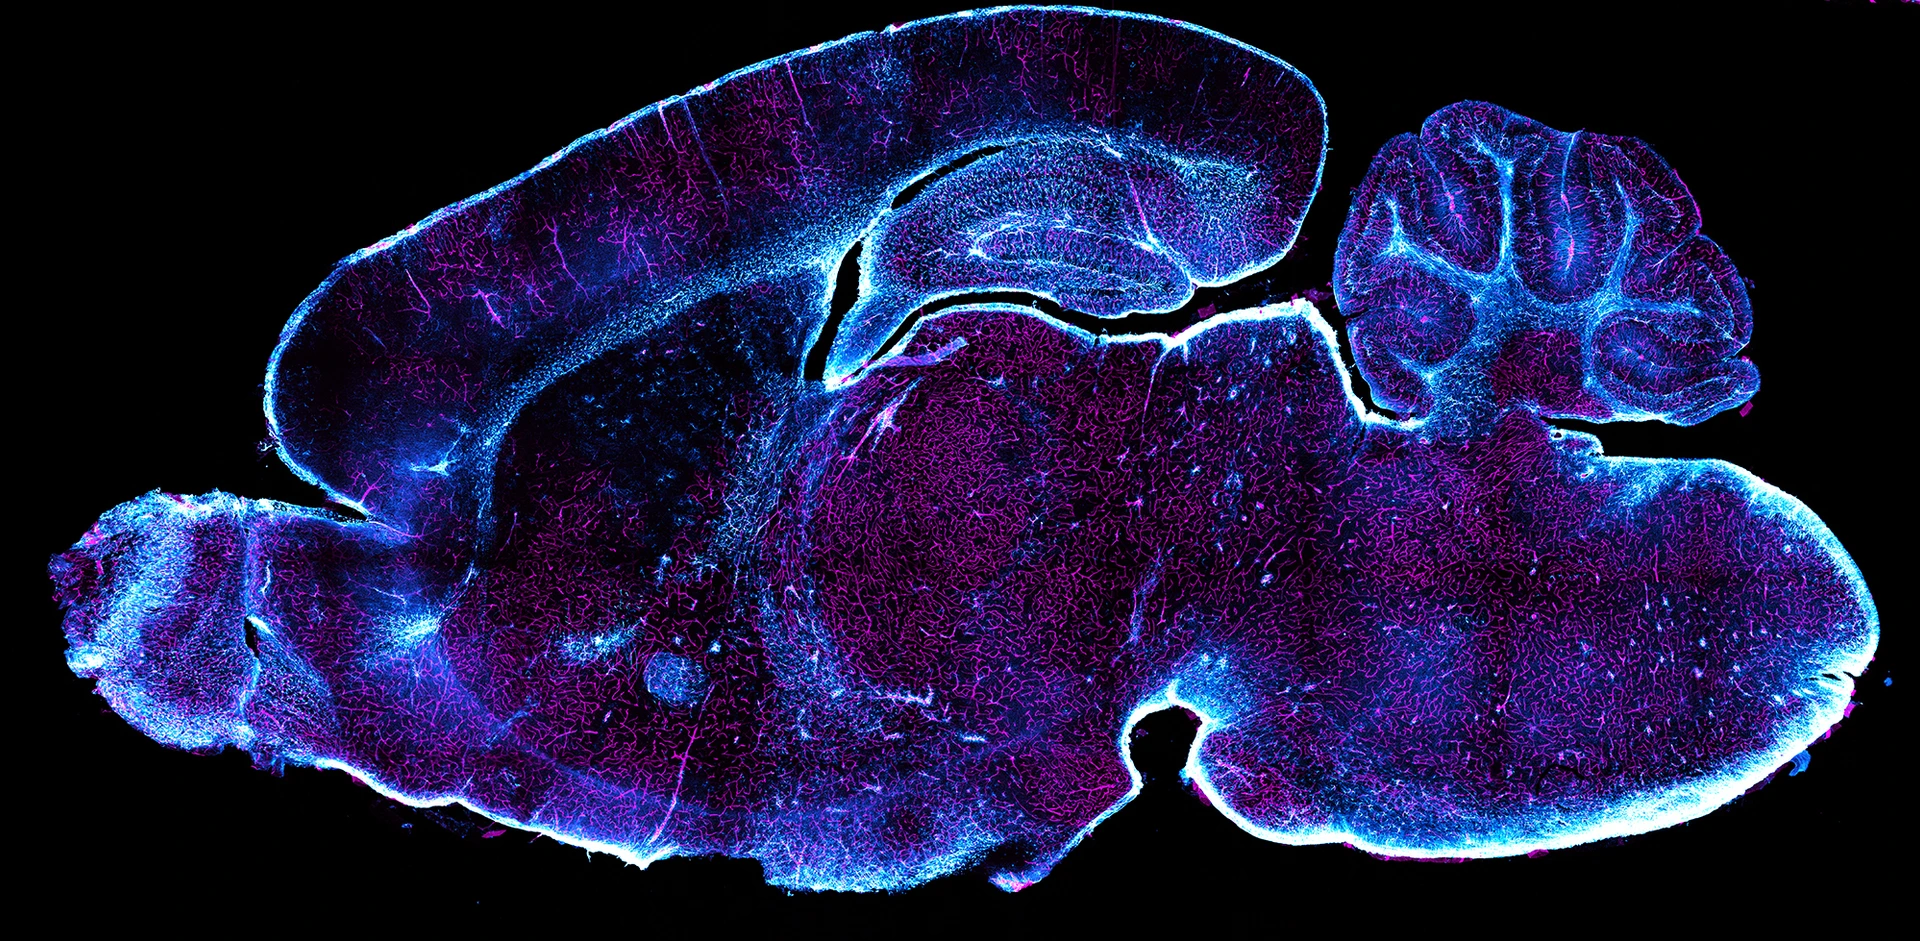

Glia Vascular System of Mouse Brain

Prof. Dr. García-Cáceres was originally recruited to the Helmholtz Munich in 2012 from the Universidad Autónoma de Madrid as a Postdoctoral Scientist, and in 2015 was promoted to lead the Astrocyte-Neuron Network Unit at the Institute for Diabetes and Obesity. Since then, she has established and consolidated her own research group focused on studying the properties and physiological consequences of the communication between neurons and astrocytes, aiming to understand the role of those glial cells in physiological and pathological aspects of brain function in the neuroendocrine control of metabolism. Her work was awarded by the prestigious ERC Starting Grant and has already resulted in a paradigm shift in how glucose gets into the brain and how hypothalamic astrocytes tune sympathetic outflow towards cardiovascular target organs for controlling blood pressure.

Obesity-associated hyperleptinemia alters the gliovascular interface of the hypothalamus to promote hypertension